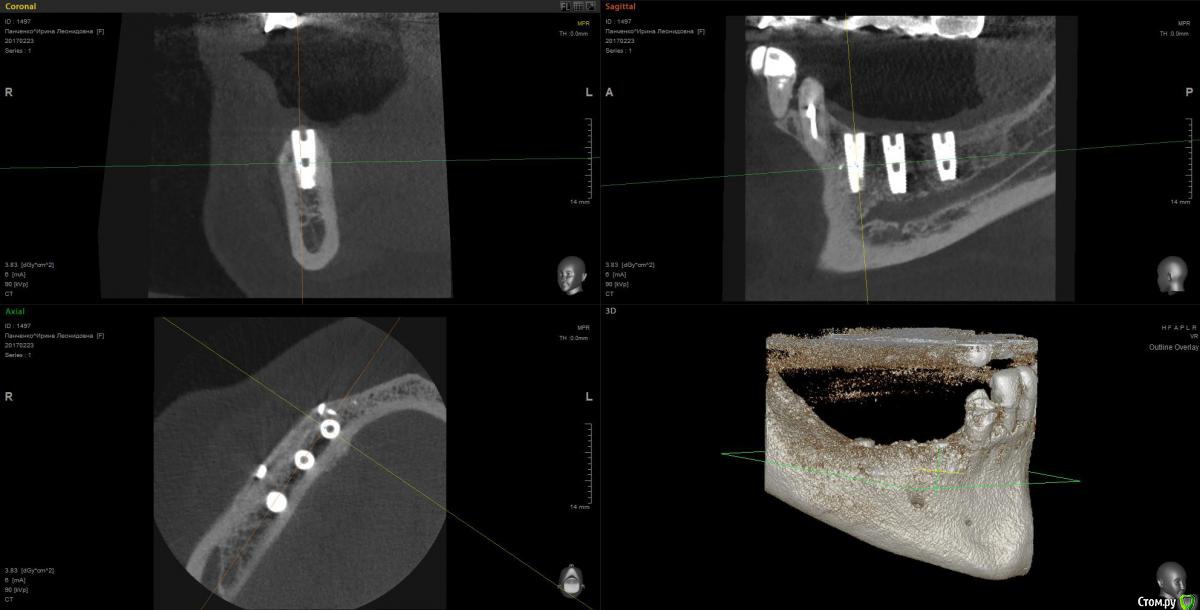

Kostoprav Опубликовано 13 марта, 2017 Поделиться Опубликовано 13 марта, 2017 рецепт сосиски: 70%биопласт by владмива +30%аутокость, мембрана hyprosorb кт до кт сразу после имплантации кт через пол года 3 Ссылка на комментарий

Kostoprav Опубликовано 14 марта, 2017 Автор Поделиться Опубликовано 14 марта, 2017 по порядку 8 Ссылка на комментарий

red_butler Опубликовано 26 марта, 2017 Поделиться Опубликовано 26 марта, 2017 Мембрану чем то фиксировали или уложили и ушили?посмотрите снимки еще раз, пины для мембраны на них видно Ссылка на комментарий